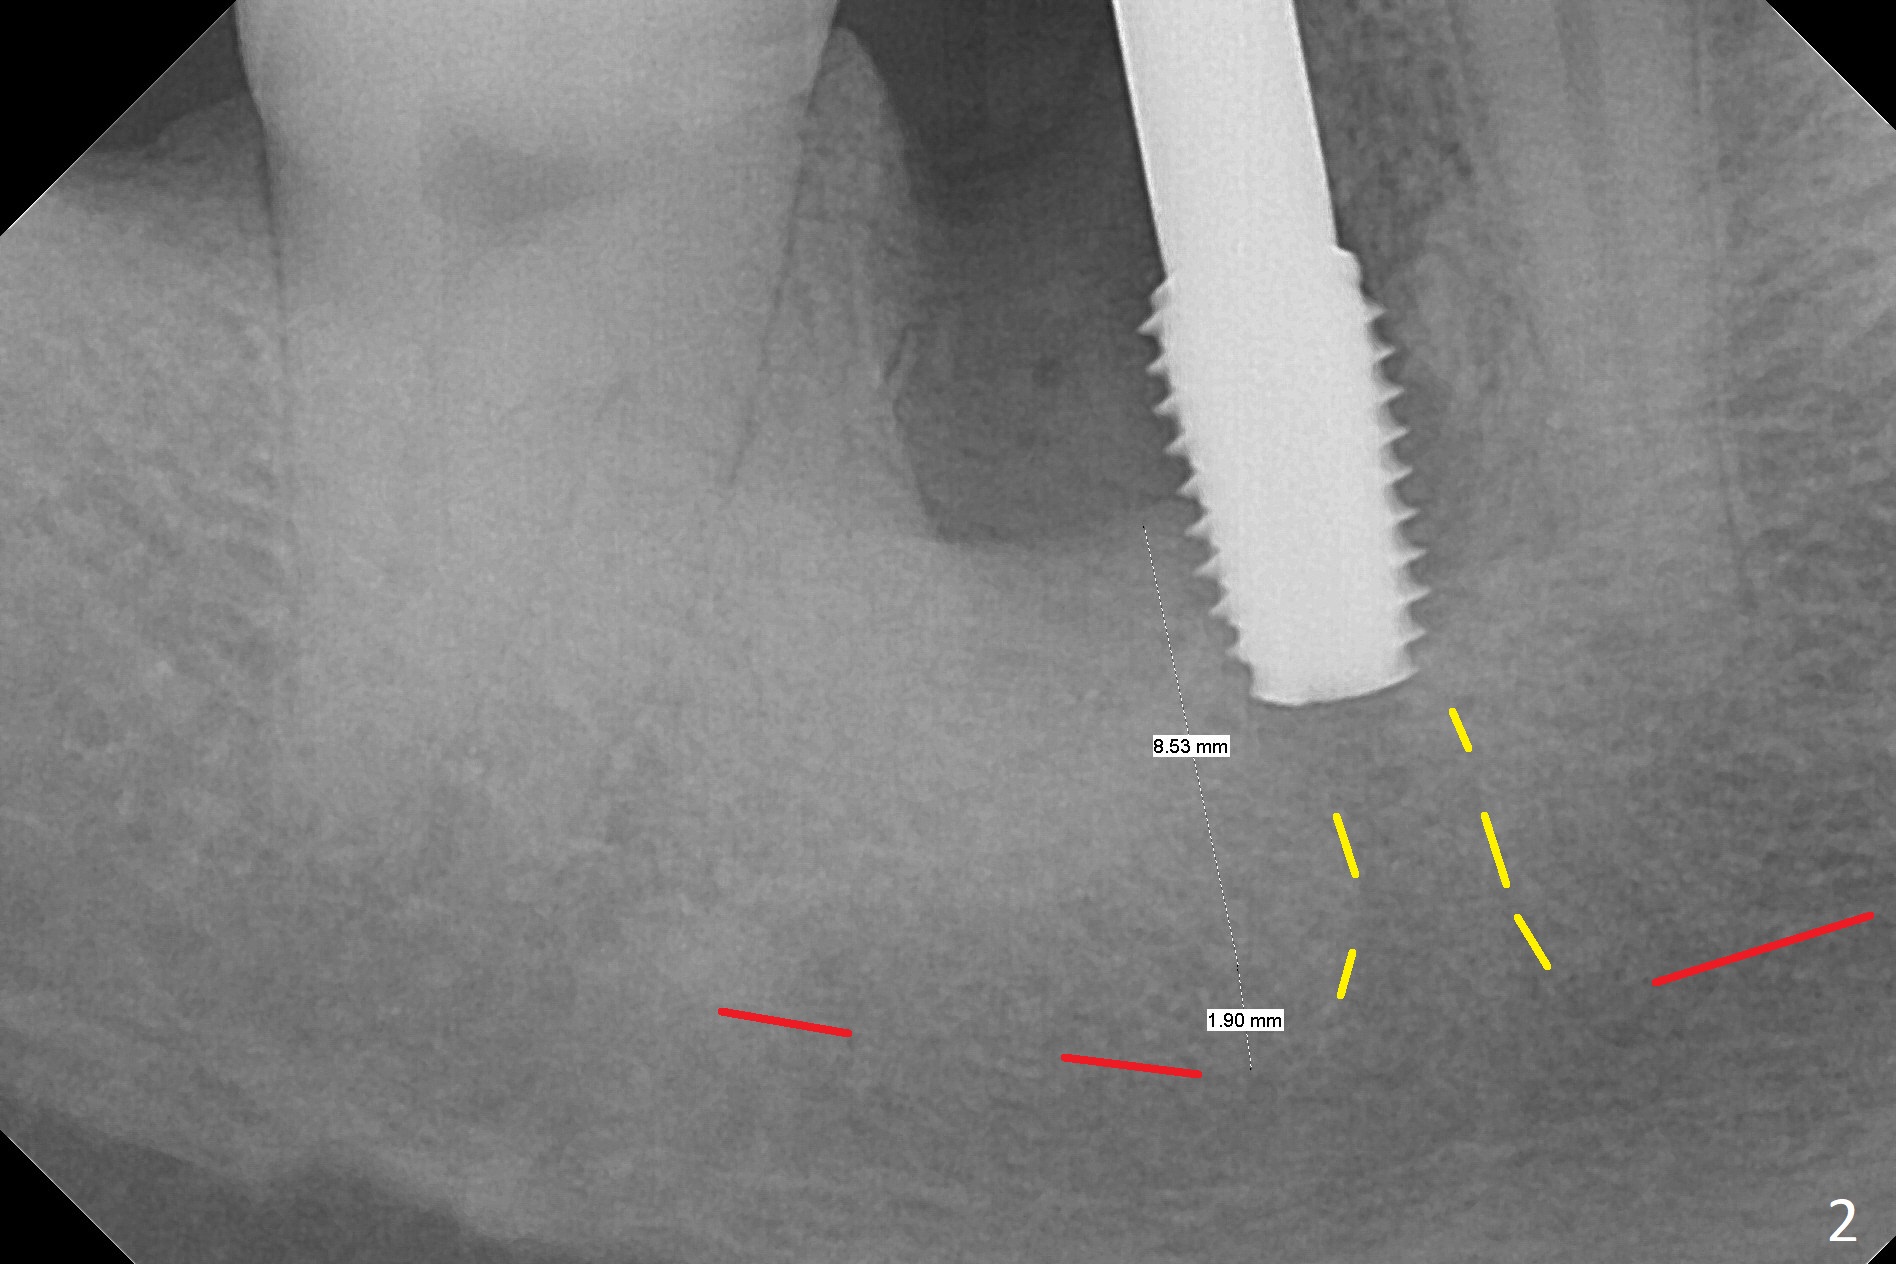

After the tooth #30 is extracted, the socket is 18 mm deep and the lingual plate is 4 mm tall. With hemorrhage, visibility of the socket, especially the bottom, is poor. The septum is almost completely defective. Following removal of the most buccal portion of the septum, osteotomy is initiated as buccal as possible, but it is mesial (Fig.1). In spite of effort to move the osteotomy distal, the osteotomy remains mesial and superficial (Fig.2 with 5 mm tap drill). Pain control is poor with infiltration. It appears that the smaller osteotomy (Fig.2 yellow line) may have extended close to the superior border of the Inferior Alveolar Canal (red line). It appears that there is 8.5 mm bone distal with ~ 2 mm clearance. After mandibular block, a new osteotomy is made distal; when a 3.8 mm drill is being used, there is hemorrhage from the osteotomy with apparent violation of the Canal integrity (Fig.3,4). But hemostasis is achieved with gauze pressure. A 5x13 mm implant is placed superficially (Fig.5) with a trace of the previous osteotomy (yellow line) and deep space created by the mesial osteotomy (*). Apparently the pathological and iatrogenic defects are filled with allograft (Fig.6 *). Guided surgery could have avoided the mesial osteotomy.